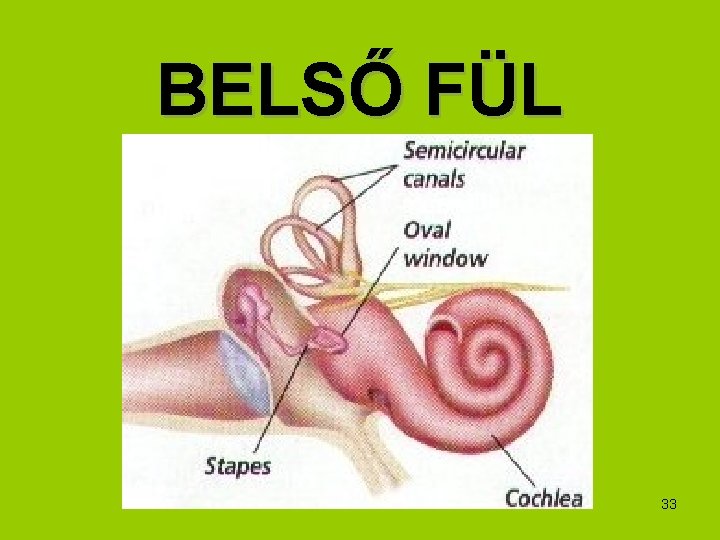

BELSŐ FÜL 33

Hallás folyamata: 1. a levegő rezgése a dobhártya és a hallócsontocskák megrezegtetésével mechanikai rezgésbe megy át 2. ez a belső fülben folyadékrezgéssé, áramlássá alakul 3. amely a szőrsejtek elhajlásával a hallás érzetét kelti Békésy György (1899 -1972) magyar származású amerikai tudós 1961 -ben Nobel-díjat kapott a fül csigájában létrejövő ingerület fizikai mechanizmusának felfedezéséért (hullám elmélet)34

Egyensúlyozás szerve: • a belső fülben a félköríves járatok hártyás labirintusának falában szőrsejtek vannak • elmozduláskor a belső folyadék tehetetlenség folytán az ellenkező oldalra folyik>> ez ad tájékoztató ingereket a központ felé 35